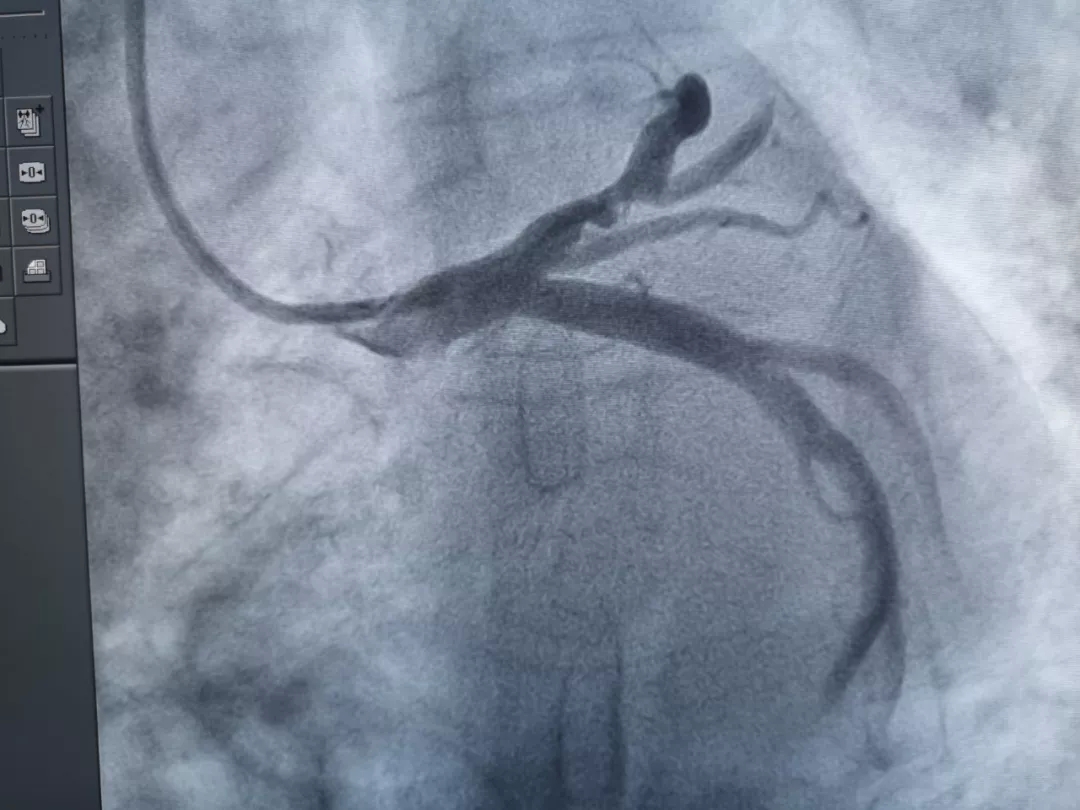

4月18日,青岛西海岸新区中医医院介入诊疗室成功实施了首例冠状动脉血管内超声检查(IVUS)技术,此项技术可精准检测血管内病变数据,使冠脉评估更精准、更严密。

69岁的张大妈因冠心病来到青岛西海岸新区中医医院心血管科住院治疗,医生在为其行冠脉造影时发现,患者冠状动脉血管前降支异常粗大,直径约为5~6mm。为更精准地判断其冠状动脉的病变情况及更好地评价术后效果,在征得患者及家属同意后,介入诊疗室医生决定采用最新的冠脉超声技术为患者进行冠脉血管内超声(IVUS)检查。

经图像分析后诊断患者斑块为纤维化混合脂质斑块,测量病变血管最大直径5.57mm,最小管腔直径2.14mm,狭窄达80%。因无该尺寸支架,建议患者选择冠脉搭桥治疗。